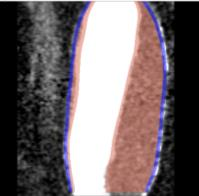

Abdominal Aortic Aneurysm (AAA) is an enlargement in the lower part of the main artery Aorta by 1.5 times its normal diameter. AAA can cause death if rupture occurs. Elective surgeries are recommended to prevent rupture based on geometrical measurements of AAA diameter and diameter growth rate. Reliability of these geometric parameters to predict the AAA rupture risk has been questioned, and biomechanical assessment has been proposed to distinguish between patients with high and low risk of rupture. Stress in aneurysm wall is the main variable of interest in such assessment. Most studies use finite element method to compute AAA stress. This requires discretising patient-specific geometry (aneurysm wall and intraluminal thrombus ILT) into finite elements/meshes. Tetrahedral elements are most commonly used as they can be generated in seemingly automated and effortless way. In practice, however, due to complex aneurysm geometry, the process tends to require time consuming mesh optimisation to ensure sufficiently high quality of tetrahedral elements. Furthermore, ensuring solution convergence requires large number of tetrahedral elements, which leads to long computation times. In this study, we focus on generation of hexahedral meshes as they are known to provide converged solution for smaller number of elements than tetrahedral meshes. Generation of hexahedral meshes for continua with complex/irregular geometry, such as aneurysms, requires analyst interaction. We propose a procedure for generating high quality patient-specific hexahedral discretisation of aneurysm wall using the algorithms available in commercial software package for mesh generation. For aneurysm cases, we demonstrate that the procedure facilitates patient-specific mesh generation within timeframe consistent with clinical workflow constraints while requiring only limited input from the analyst.